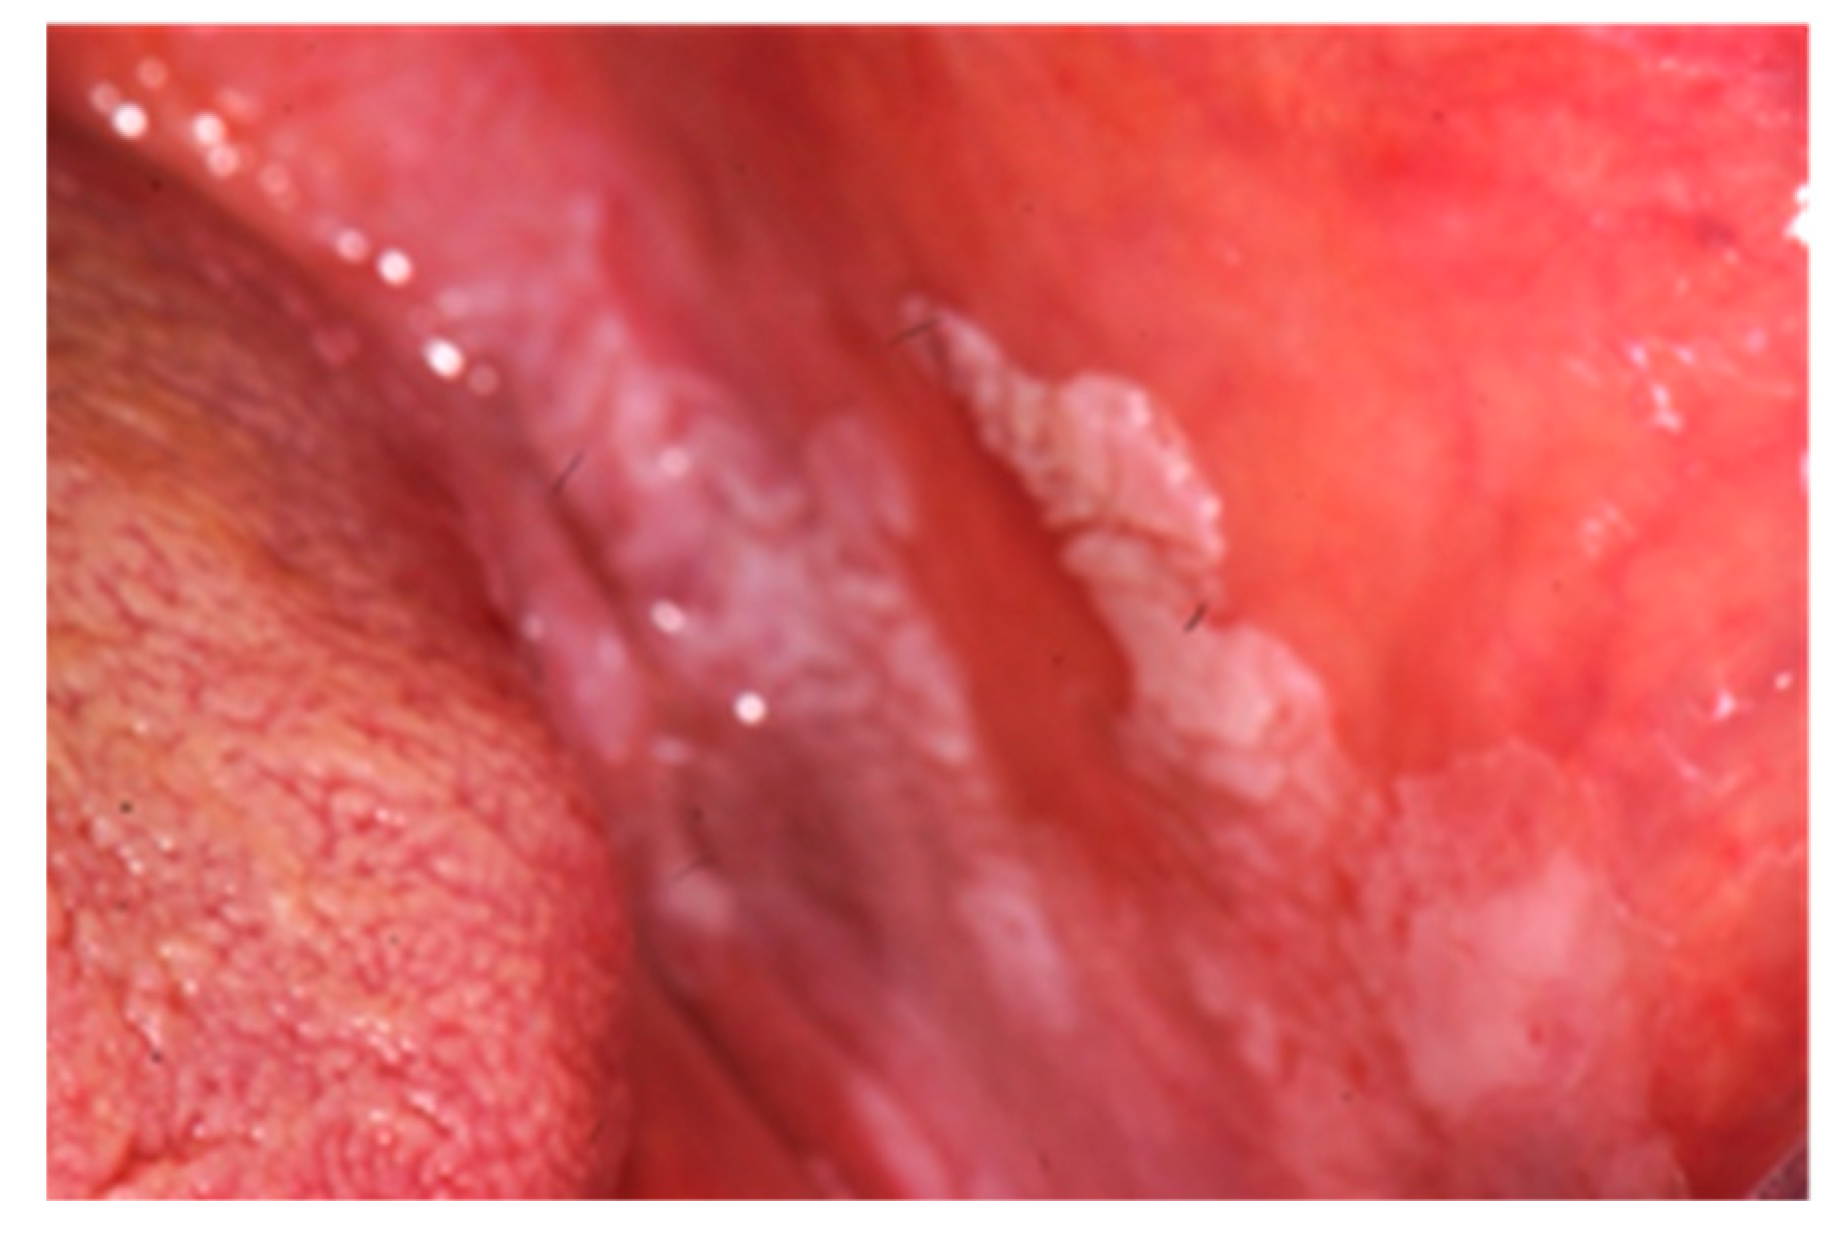

| Specific manifestations | Oral manifestations | Crohn’s disease | Ulcerative colitis |

| Cobblestoning the mucosa | X | ||

| Granulomatous cheilitis | X | ||

| Mucosal tags | X | ||

| Pyostomatitis vegetans | X | ||

| Unspecific manifestations | Deep oral fissuring | X | |

| Cheilitis angularis | X | X | |

| Dental caries | X | X | |

| Mucogingivitis | X | X | |

| Periodontitis | X | X | |

| Lichen planus | X | X | |

| Dysphagia | X | X | |

| Dry mouth | X | X | |

| Halitosis | X | X | |

| Taste changes | X | X | |

| Aphthous ulcerations | X | X |